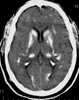

Primary familial brain calcification (PFBC), also known as familial idiopathic basal ganglia calcification (FIBGC) and Fahr's disease, is a rare, genetically dominant, inherited neurological disorder characterized by abnormal deposits of calcium in areas of the brain that control movement. Through the use of CT scans, calcifications are seen primarily in the basal ganglia and in other areas such as the cerebral cortex. [Source: Wikipedia ]